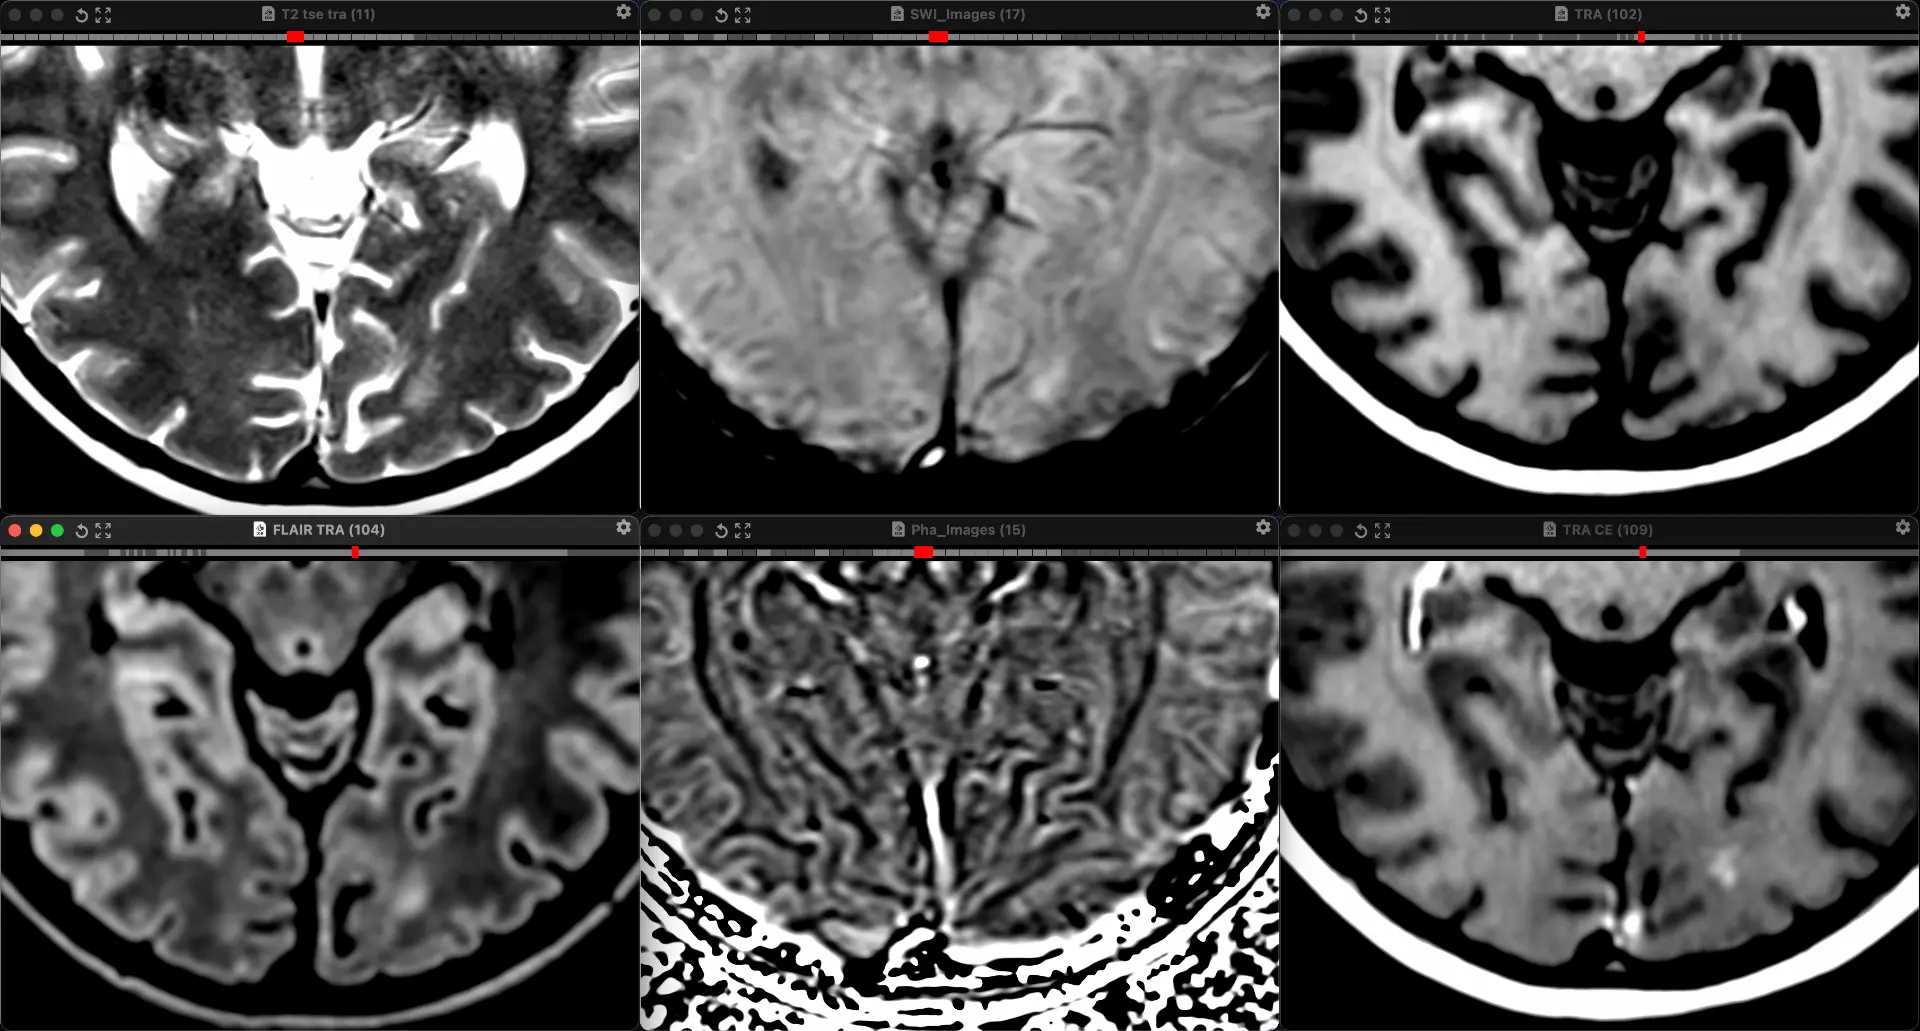

Женщина 32 года. Больной считает себя с 2024 г, когда стала отмечать онемение угла рта. Со слов пациентки ей был предварительно выставлен диагноз - РС, но дополнительных методов обследования и специфического лечения не проводилось. В настоящее время жалоб нет. В исследовании от октября 2024 отмечался очаг в левой затылочной доле с выраженным контрастированием, в настоящее время этот же очаг отмечается с сохраняющимся контрастированием. Формально - есть выполнение критериев диссеминации и в пространстве (юкстакортикальный и перивентрикулярный очаги есть), и во времени (есть усиливающиеся и неусиливающиеся очаги), клиника тоже вполне укладывается. Но! Найти в литературе подобных случаев мне не удалось, видел сам и максимум, что находил в литературе - полгода контрастирования. Получается, мы имеем дело с крайне атипичным рассеянным склерозом, или это не рассеянный склероз. А тогда что? Сосудистая мальформация не вариант - на SWI не видать. Какая-то ганглиоглиома? А другие очаги тогда что? Есть соображения? Кстати, диффузия стойко повышенная, и на б1000 почти не видно (изо). На Т2 не меняется